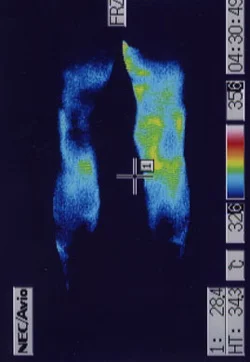

慢性前立腺炎は原因不明と言われています。

慢性前立腺炎は、鍼治療でよくなります。

前立腺の急性炎症のあとにおきた陰部神経痛です。